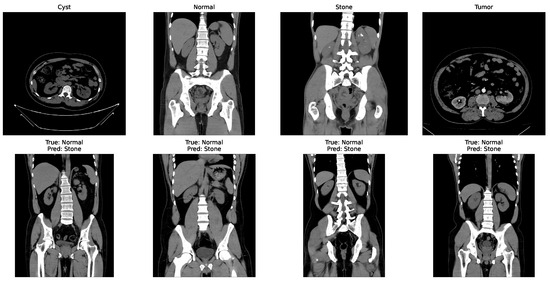

Some of the examples of the ct images of four classes are shown in Figure 3.

Figure 3.

Examples of cyst, normal, stone, and tumor CT image.

In the matrix, the diagonal elements represent correctly classified instances, and the rest of the elements indicate misclassifications. The incorrectly classified numbers are 18, 18, and 21 for baseline, Dataset A, and Dataset B, respectively. Although the model performs consistently well across all datasets, a slightly higher misclassification rate is observed in the stone class. This is mainly attributed to the smaller sample size of the stone category, which limits the model’s ability to learn its feature variability, even after applying SMOTE balancing. Additionally, the visual inspection of misclassified cases shown in Figure 9 revealed that some stone images share overlapping visual characteristics with cyst and tumor classes, such as low-contrast textures and irregular boundaries, making them challenging to distinguish even for deep learning models.

Figure 9.

Some incorrectly classified images.